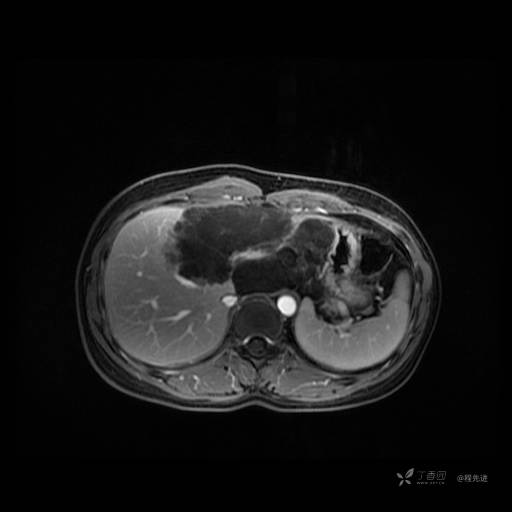

MR平扫+增强

每个序列一张图像(图像太多了,恕不一一发上来)